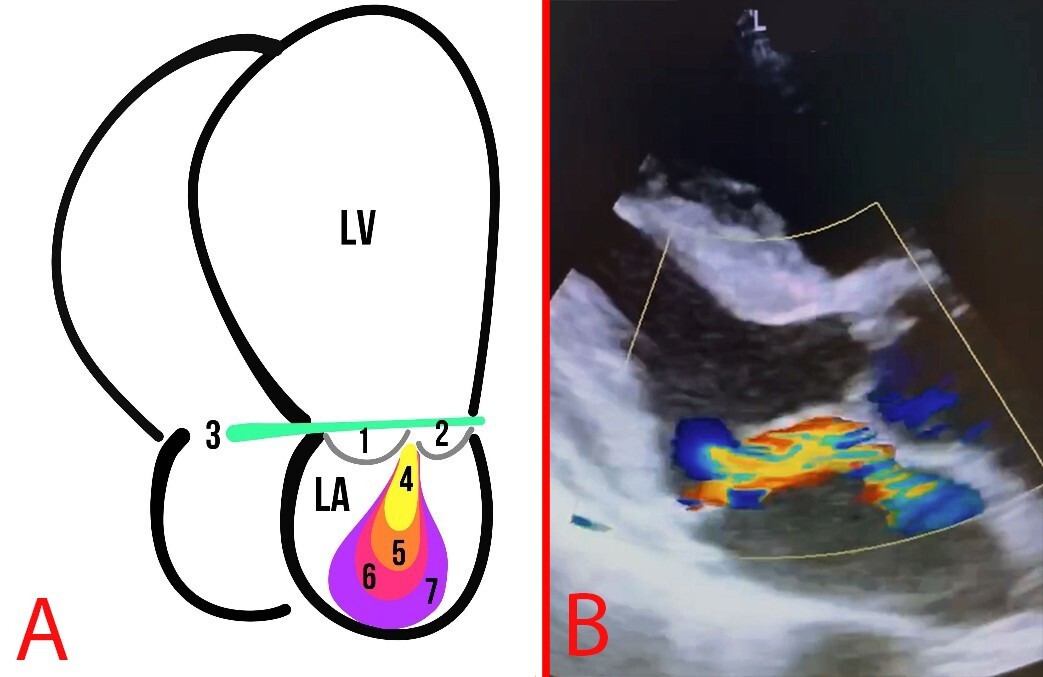

Two-dimensional (2D) echocardiography imaging is the modality of choice for evaluating the MR etiology and mechanism. Meanwhile, MR severity is semi-quantitatively assessed by eyeballing the proportion of the left atrium (LA) area occupied by the regurgitant jet on 2D/color Doppler imaging [30]. MVP may result in MR, both acute and chronic. With a prolonged course of the disease, the left atrium changes, becoming dilated due to increased pressure. MR is usually evaluated based on the guidelines of the American Society of Echocardiography (Fig. 7) [31].

Fig. 7. MR. (A) Schematic representation of MR grades: The numbers 1 and 2 indicate the MVP leaflets; 3 depicts the mitral annulus line; 4, first degree of MR; 5, second degree of MR; 6, third degree of MR; 7, fourth degree of MR. (B) Echocardiography of a patient with MVP and MR.